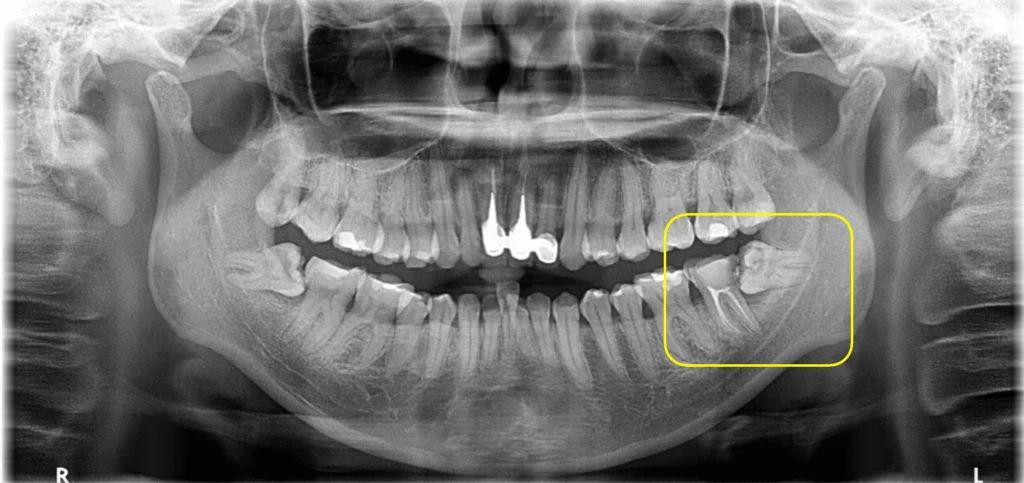

最後可講返一個小貼士。北上拔智齒之前,最好先喺香港照下X光,了解智齒位置同結構,帶去畀北上牙醫睇,更方便佢判斷要唔要麻醉、點樣做。拔完之後,休息夠、補水、唔好即刻大力咀嘢,傷口自然好得快。麻醉唔係可怕嘢,只要處理得好,拔智齒可以係一個相對輕鬆嘅過程。